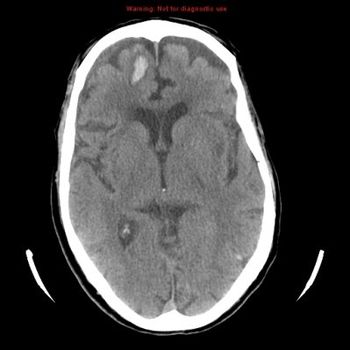

A new genetic analysis found five new genetic variants that raise the risk for gliomas. One of the five was associated with a sharply increased risk for glioblastoma.